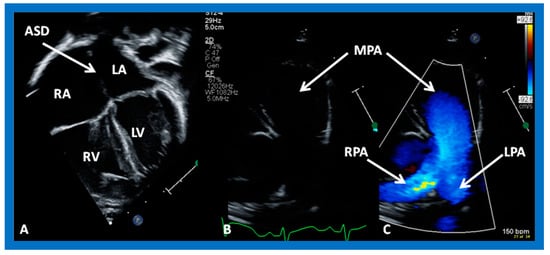

2. Diagnosis